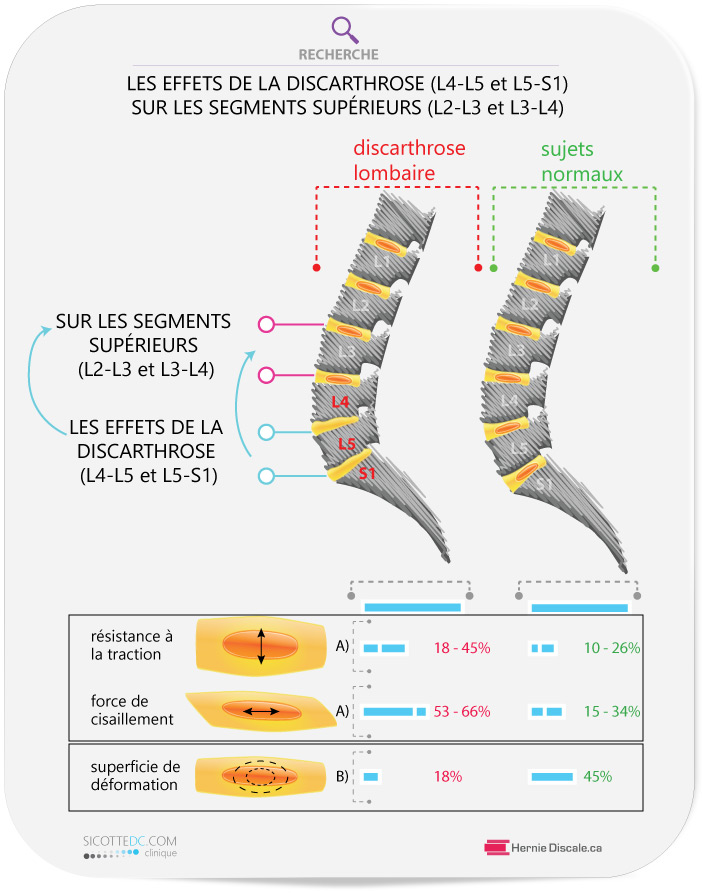

Une étude se penche sur les effets de la discarthrose (L4-L5 et L5-S1) sur les niveaux supérieurs (L2-L3 et L3-L4) de la colonne vertébrale lombaire.

- la progression de l’arthrose lombaire entraîne plusieurs effets : crée de l’hypermobilité des segments vertébraux supérieurs (*1),

- * (voir image à gauche)